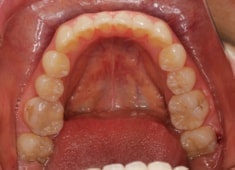

治療前